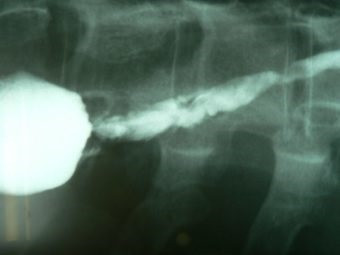

Dilatación esofágica con balón

Envíado por Dr. Carlos Miguel Zavaleta Consuegra